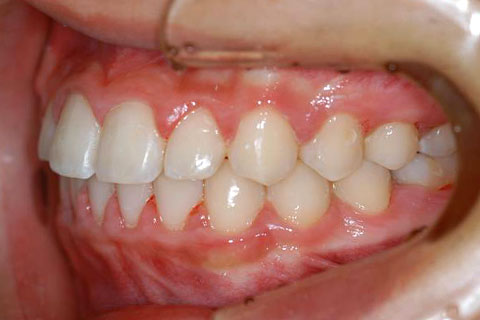

受け口(反対咬合)の症例

症例一覧